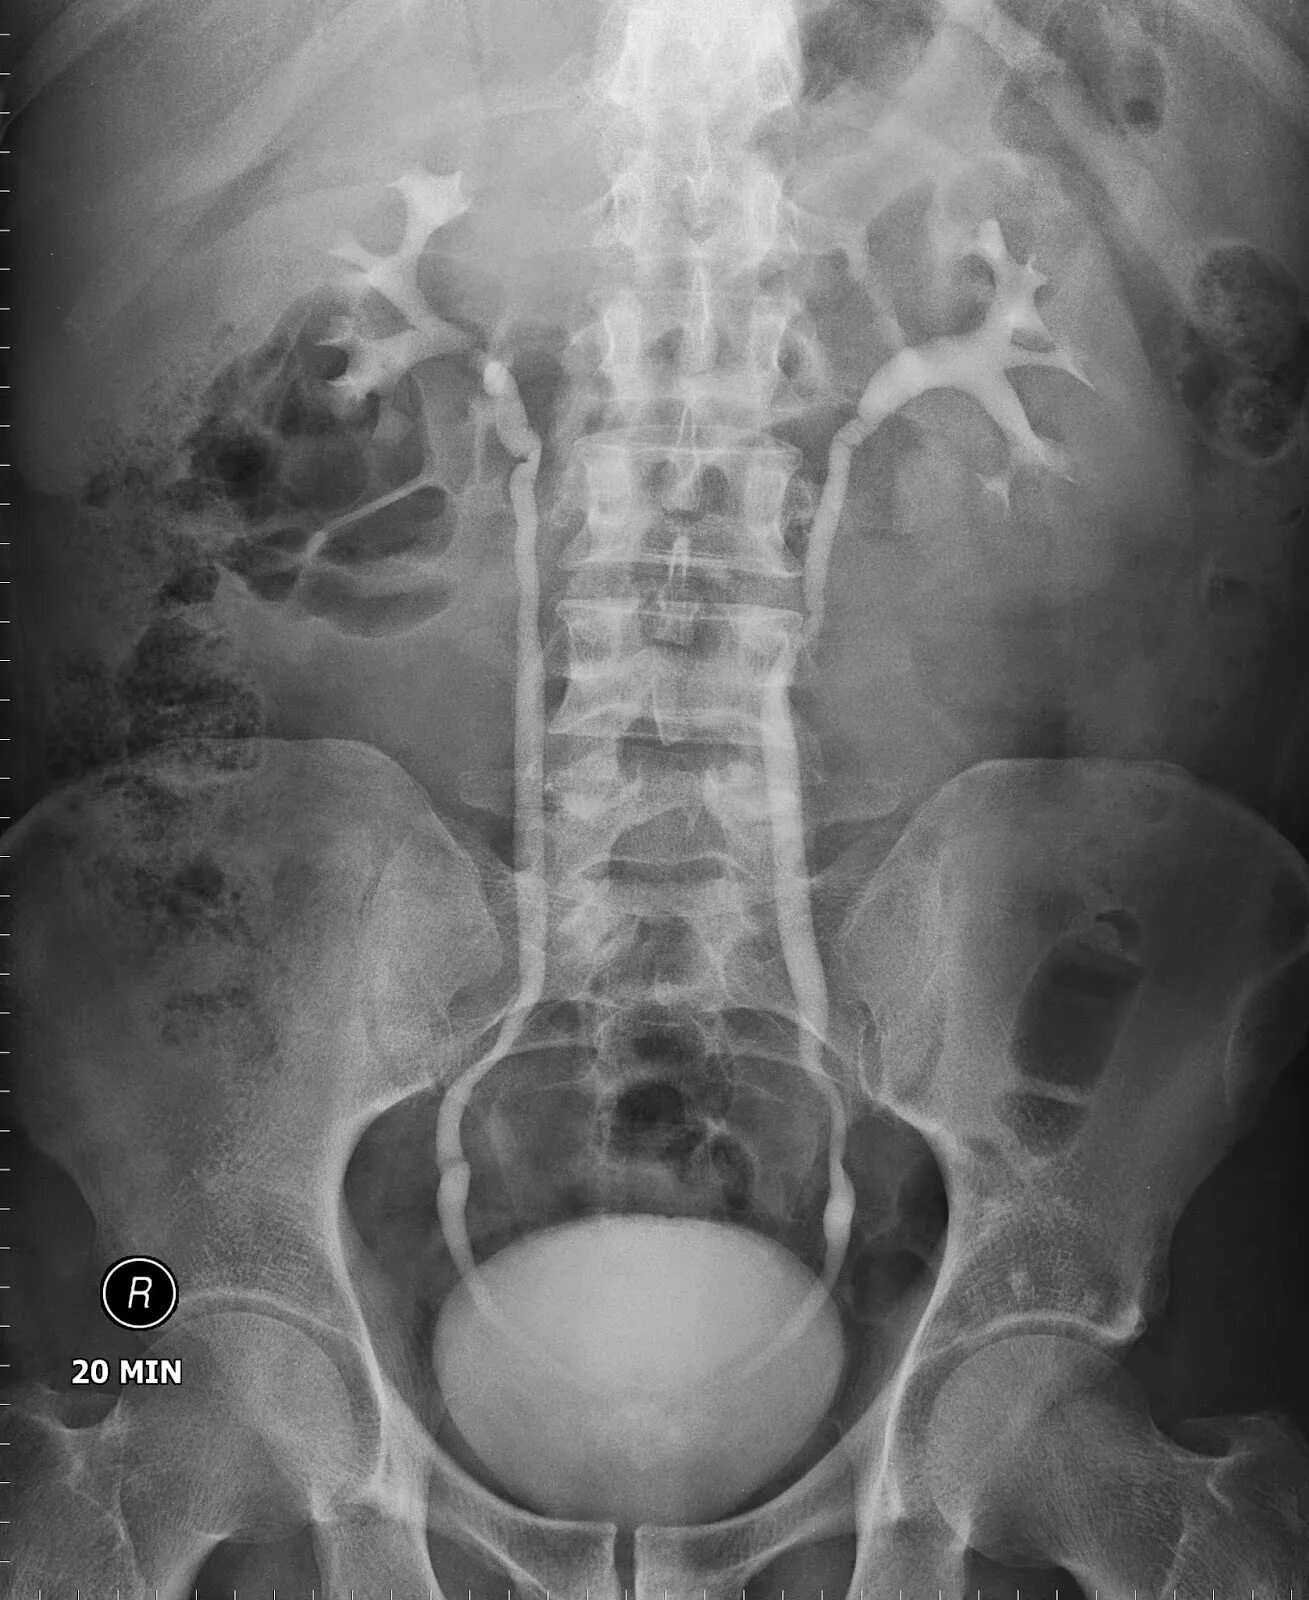

Урография с контрастом